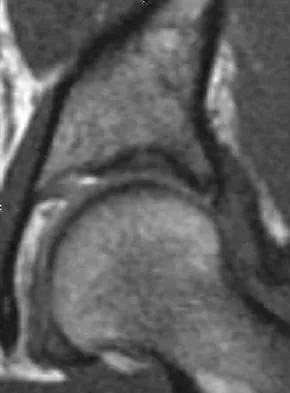

A sagittal T1-weighted MRI scan of the knee joint is shown in Figure 23. What structure is identified by the arrow?

A patient notes pain under the first metatarsophalangeal joint following a soccer injury. The MRI scans shown in Figures 27a and 27b reveal what pathologic finding?